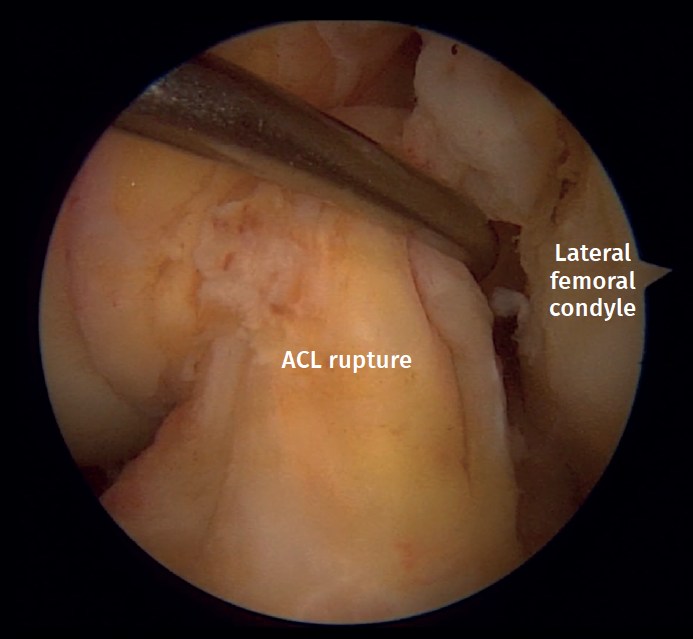

Five ACL ruptures were diagnosed in type II fractures, with 4 complete ligamentous tears (total disruption of fibers) found during arthroscopy (Figure 5). In addition, there was 1 displaced tibial eminence avulsion fracture (McKeever II)(8)(Figure 6A). PCL, LCL and MCL injuries were not found in this cohort. Likewise, neurovascular structures remained intact in all the cases studied.

Figure 5. Left knee anterior cruciate ligament (ACL) rupture. View from the anterolateral portal. Probe placed in the anteromedial portal.

All ligamentous disruptions required arthroscopically assisted reduction and minimally invasive fixation of the fracture followed by ACL reconstruction with a hamstring autograft. The displaced tibial eminence avulsion received arthroscopic treatment with a suture fixation technique (Figure 6B).